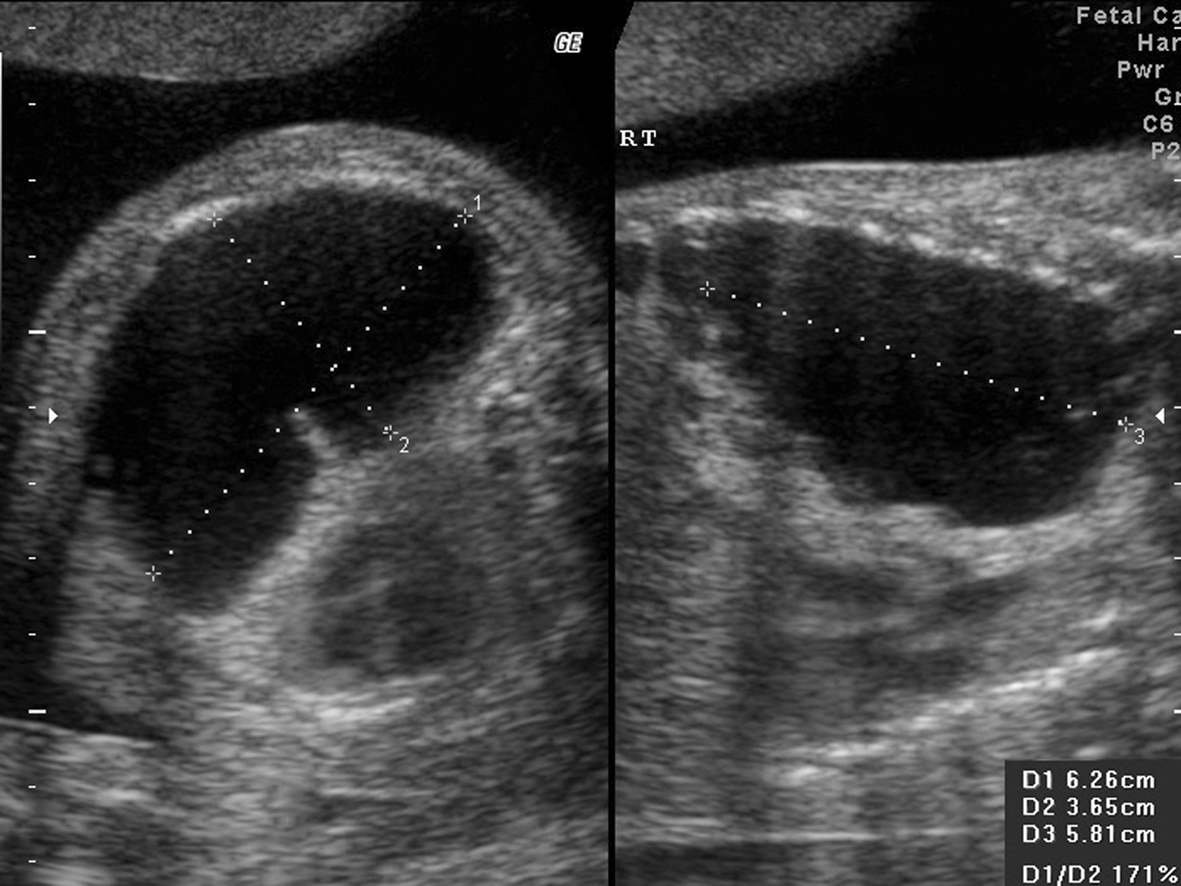

1.胎儿肺部异常 ①I型(大囊肿型):胸腔内见囊性或囊实混合性肿块,囊肿直径≥2 cm(图1);②Ⅱ型(小囊肿型):胸腔内见囊实混合性肿块,囊肿直径在5mm~2 cm间(图2);③III型(实质型或微囊肿型):胸腔内强回声实性肿物,与正常肺组织边界清晰,使用高频探头可观察到强回声实性肿块内部弥漫分布筛孔状无回声区,最大囊肿直径<5 mm(图3、4)。

图1 右侧胸腔CCAM I型: 孕22周6天